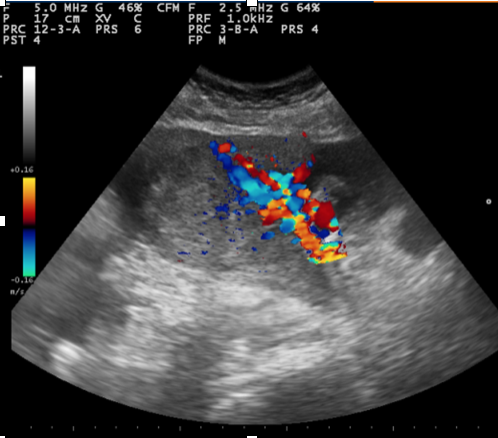

1. Mujer de 62 años; distensión abdominal; carcinoma de ovario.

2. Mujer de 46 años; dolor abdominal; masa ovárica a estudio.

3. Mujer 19 años; asintomática, ecografía durante curso de formación; hamartoma.

4. Mujer 32 años; dolor abdominal; quiste ovárico simple.

5. Mujer 27 años; ITU de repetición; ovario poliquístico.

La ecografía ginecológica vía abdominal puede ser muy útil en Atención Primaria para la valoración de problemas frecuentes como los trastornos menstruales o el dolor abdominal. También se puede identificar masas ováricas de forma incidental al realizar ecografía por otro motivo. En el caso de encontrar, como ha sucedido con relativa frecuencia, patología anexial es pertinente conocer las características ecográficas que sugieran malignidad o benignidad para su correcto manejo.